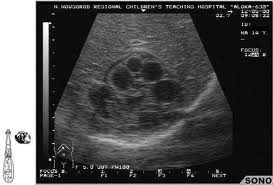

Ультразвуковое исследование печени

Этот метод используется для обследования органов брюшной полости, позволяя выявить увеличение печени или кисты.

Срез компьютерной томографии печени с эхинококковой кистой.